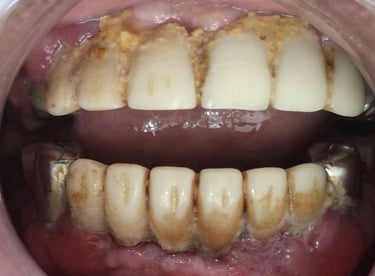

Professional Teeth Cleaning in Shyamal, Ahmedabad

Gentle, properly performed and tailored teeth cleaning for each person giving you comfort, safety and visible results. People from Shyamal and nearby areas of Ahmedabad visit our clinic for comfortable and very effective teeth cleaning.

After

All images shown here are real teeth cleaning cases treated at our clinic with patient consent.

Professional teeth cleaning helps remove plaque, tarter, and surface stains that regular at home brushing can not.

At Shree Dental Care, teeth cleaning is performed gently with focus on patient experience, comfort and long term oral health.